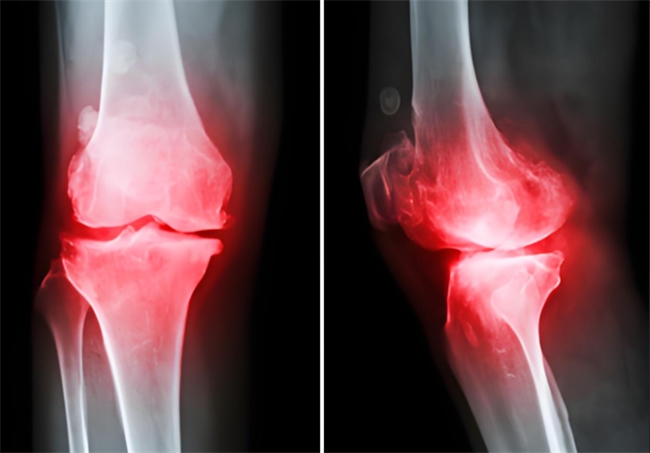

上下楼梯时膝盖“咯吱”响,蹲起时关节又酸又胀,阴雨天关节疼得连走路都费劲……这些看似是“小毛病”,其实可能是骨关节炎发出的预警。如果没能及时干预,病情会持续发展,进而导致关节软骨进一步磨损;关节症状也会从偶尔不适变成持续疼痛,严重时甚至会影响日常活动。那么,骨关节炎该如何治疗?氨糖是临床中常用于管理骨关节炎的核心治疗成分之一。但它还分OTC硫酸氨糖和氨糖软骨素钙片,到底OTC硫酸氨糖和氨糖软骨素钙片的功效和作用有什么不同?

面对频繁出现的关节疼痛、僵硬、红肿等骨关节炎的预警信号,患者一定及时就医治疗。一旦确诊骨关节炎,需在明确OTC硫酸氨糖和氨糖软骨素钙片的功效差异后,在医生指导下优选以维固力为代表的原研OTC硫酸氨糖对症治疗,缓解疼痛、僵硬等不适,并延缓关节磨损,进而延长关节使用寿命。当然,药物干预外,生活方式调整也不能少,注意控制体重以减少关节负担、避免久站久坐、适当进行对关节友好的锻炼等,双管齐下才能更好地守护关节健康。